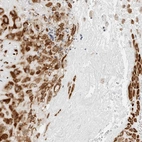

Immunohistochemistry analysis in human placenta and liver tissues using HPA027824 antibody. Corresponding P4HA2 RNA-seq data are presented for the same tissues.